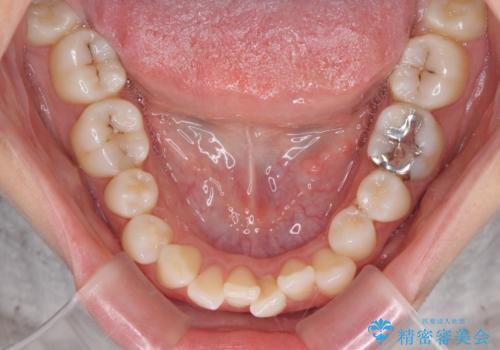

口元の突出感のない、すっきりとした仕上がりとなりました。